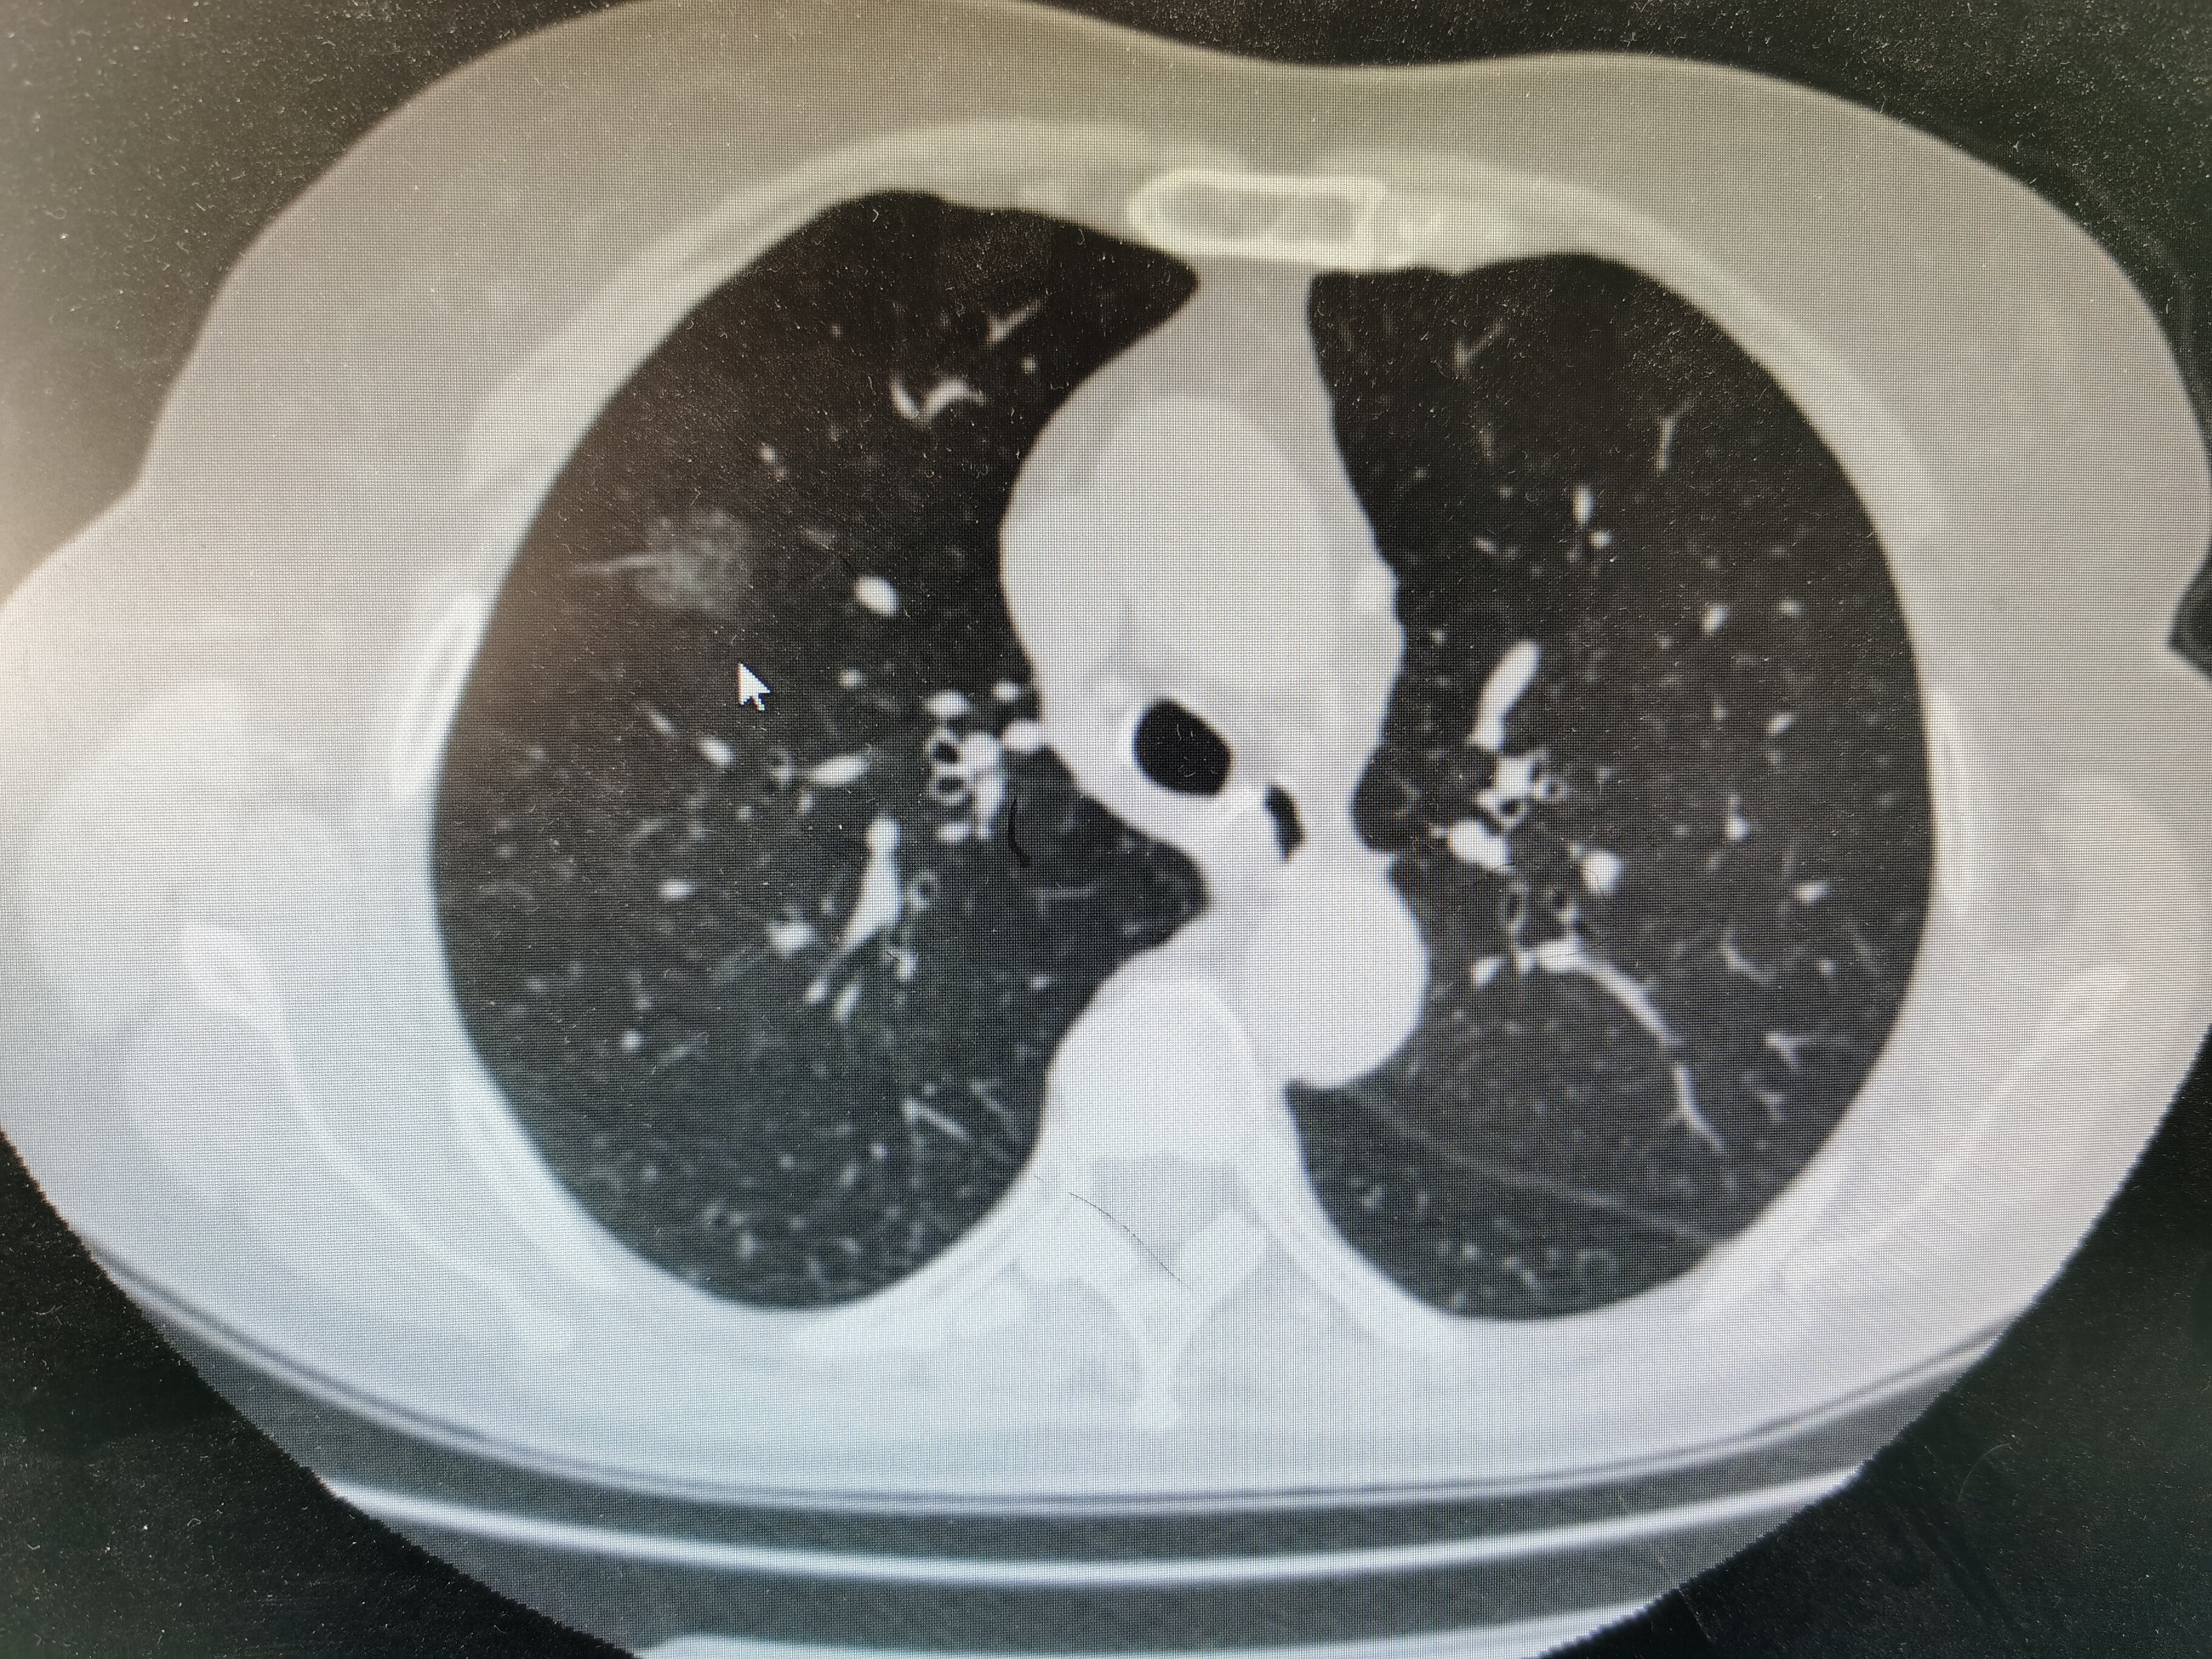

肺部结节是指影像学上直径小于三厘米的阴影。

肺部结节的大小一般在三厘米以下,可以通过CT检查出来。肺部结节表示患者肺部发生的病灶,分为良性结节和恶性结节。通常良性结节不会对患者产生过大的不良影响,而恶性结节患者需要及时进行治疗,避免病情加重。

肺有结节的严重程度要根据结节的性质来判断。